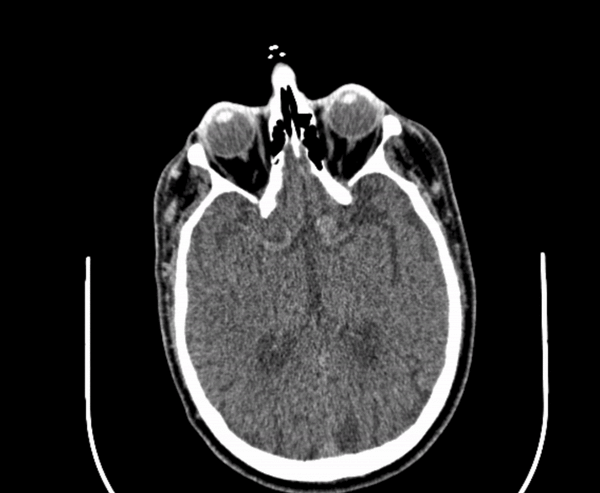

If a picture is worth 1000 words, how many words is a DICOM?

A tool for interactive case presentations